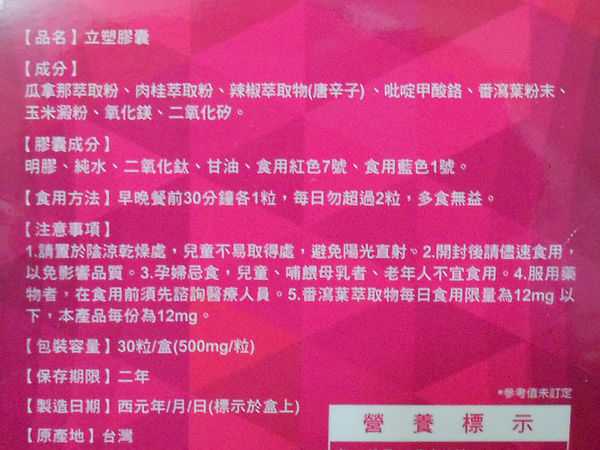

Supercut塑魔纖立塑膠囊的成分有:瓜拿那萃取粉、肉桂萃取粉、辣椒萃取物(唐辛子)、吡啶甲酸鉻、番瀉葉粉末、玉米澱粉、氧化鎂、二氧化矽。

之前上過相關課程,成分表是依照每項成分的多寡來排列順序,排在最前面的就是產品的主要成分!

食用方式:早晚餐前30分鐘各1粒,每日不超過2粒。(多食無益)

番瀉葉萃取物每日食用限量為12mg以下,

番瀉葉萃取物每日食用限量為12mg以下,